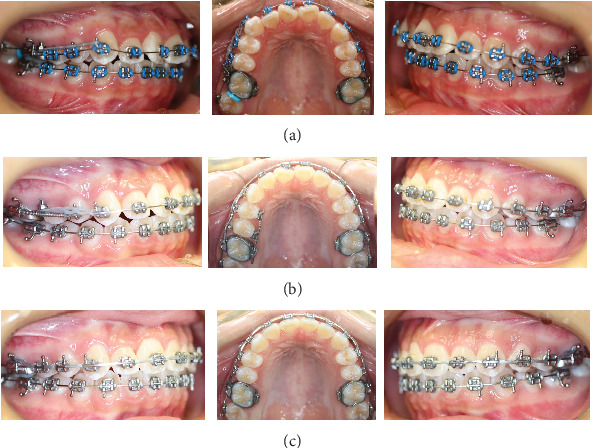

Background: Treatment of Class II subdivision can present a challenge for the clinician because of its asymmetry and possible midline deviation. This case report documents the use of a computer-aided design/computer-aided manufacturing (CAD/CAM) surgical guide for miniscrew placement in a Class II subdivision treatment. Case Presentation: A 17-year and 1-month-old female presented with a skeletal Class I relationship, but mild mandibular skeletal and dental midline shift to the right relative to the facial midline. A full-step Class II molar relationship on the right side and slight Class III molar relationship on the left side and a 4.0 mm deficiency of space in the maxillary were noticed. Using CAD/CAM technology, a surgical guide was designed virtually and 3D printed for predrilling. With the surgical guide, one ø1.3 mm twist drill was chosen to prepare a 4-5 mm deep hole in the alveolar process distobuccal to the maxillary right second premolar. A ø1.4 mm × 8.0 mm miniscrew was inserted into the prepared hole. With this miniscrew, the unilateral Class II relationship was corrected successfully by distalization of the unilateral maxillary dentition on the Class II side after 13 months of treatment. Conclusion: Application of CAD/CAM surgical guide is very helpful for placement of the miniscrew. Class II subdivision may be treated by distalizing unilateral maxillary dentition on the Class II side using the miniscrew.